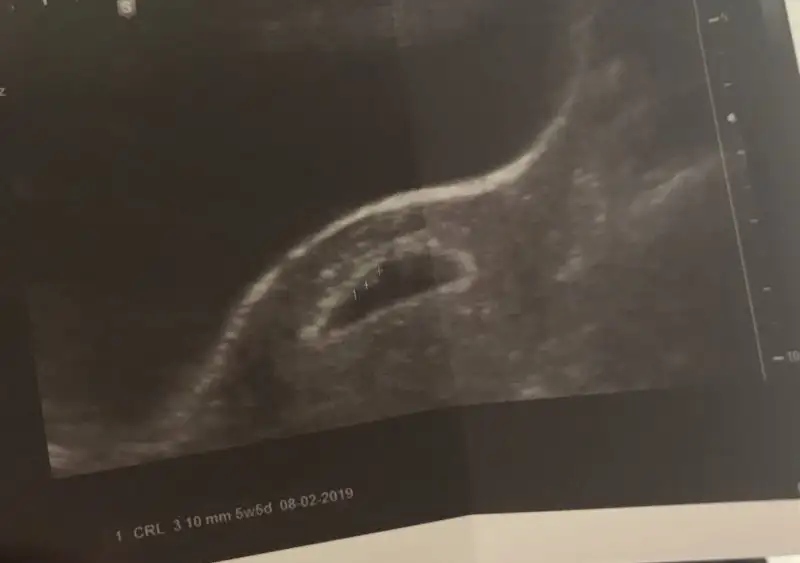

• E4145049-27AA-4896-B726-D295D8C580E5.webp

E4145049-27AA-4896-B726-D295D8C580E5.webp

9,5 KB · Görüntüleme: 499

Sanırım oldu :) bu fotoda 5+5 gnlüktüm :)